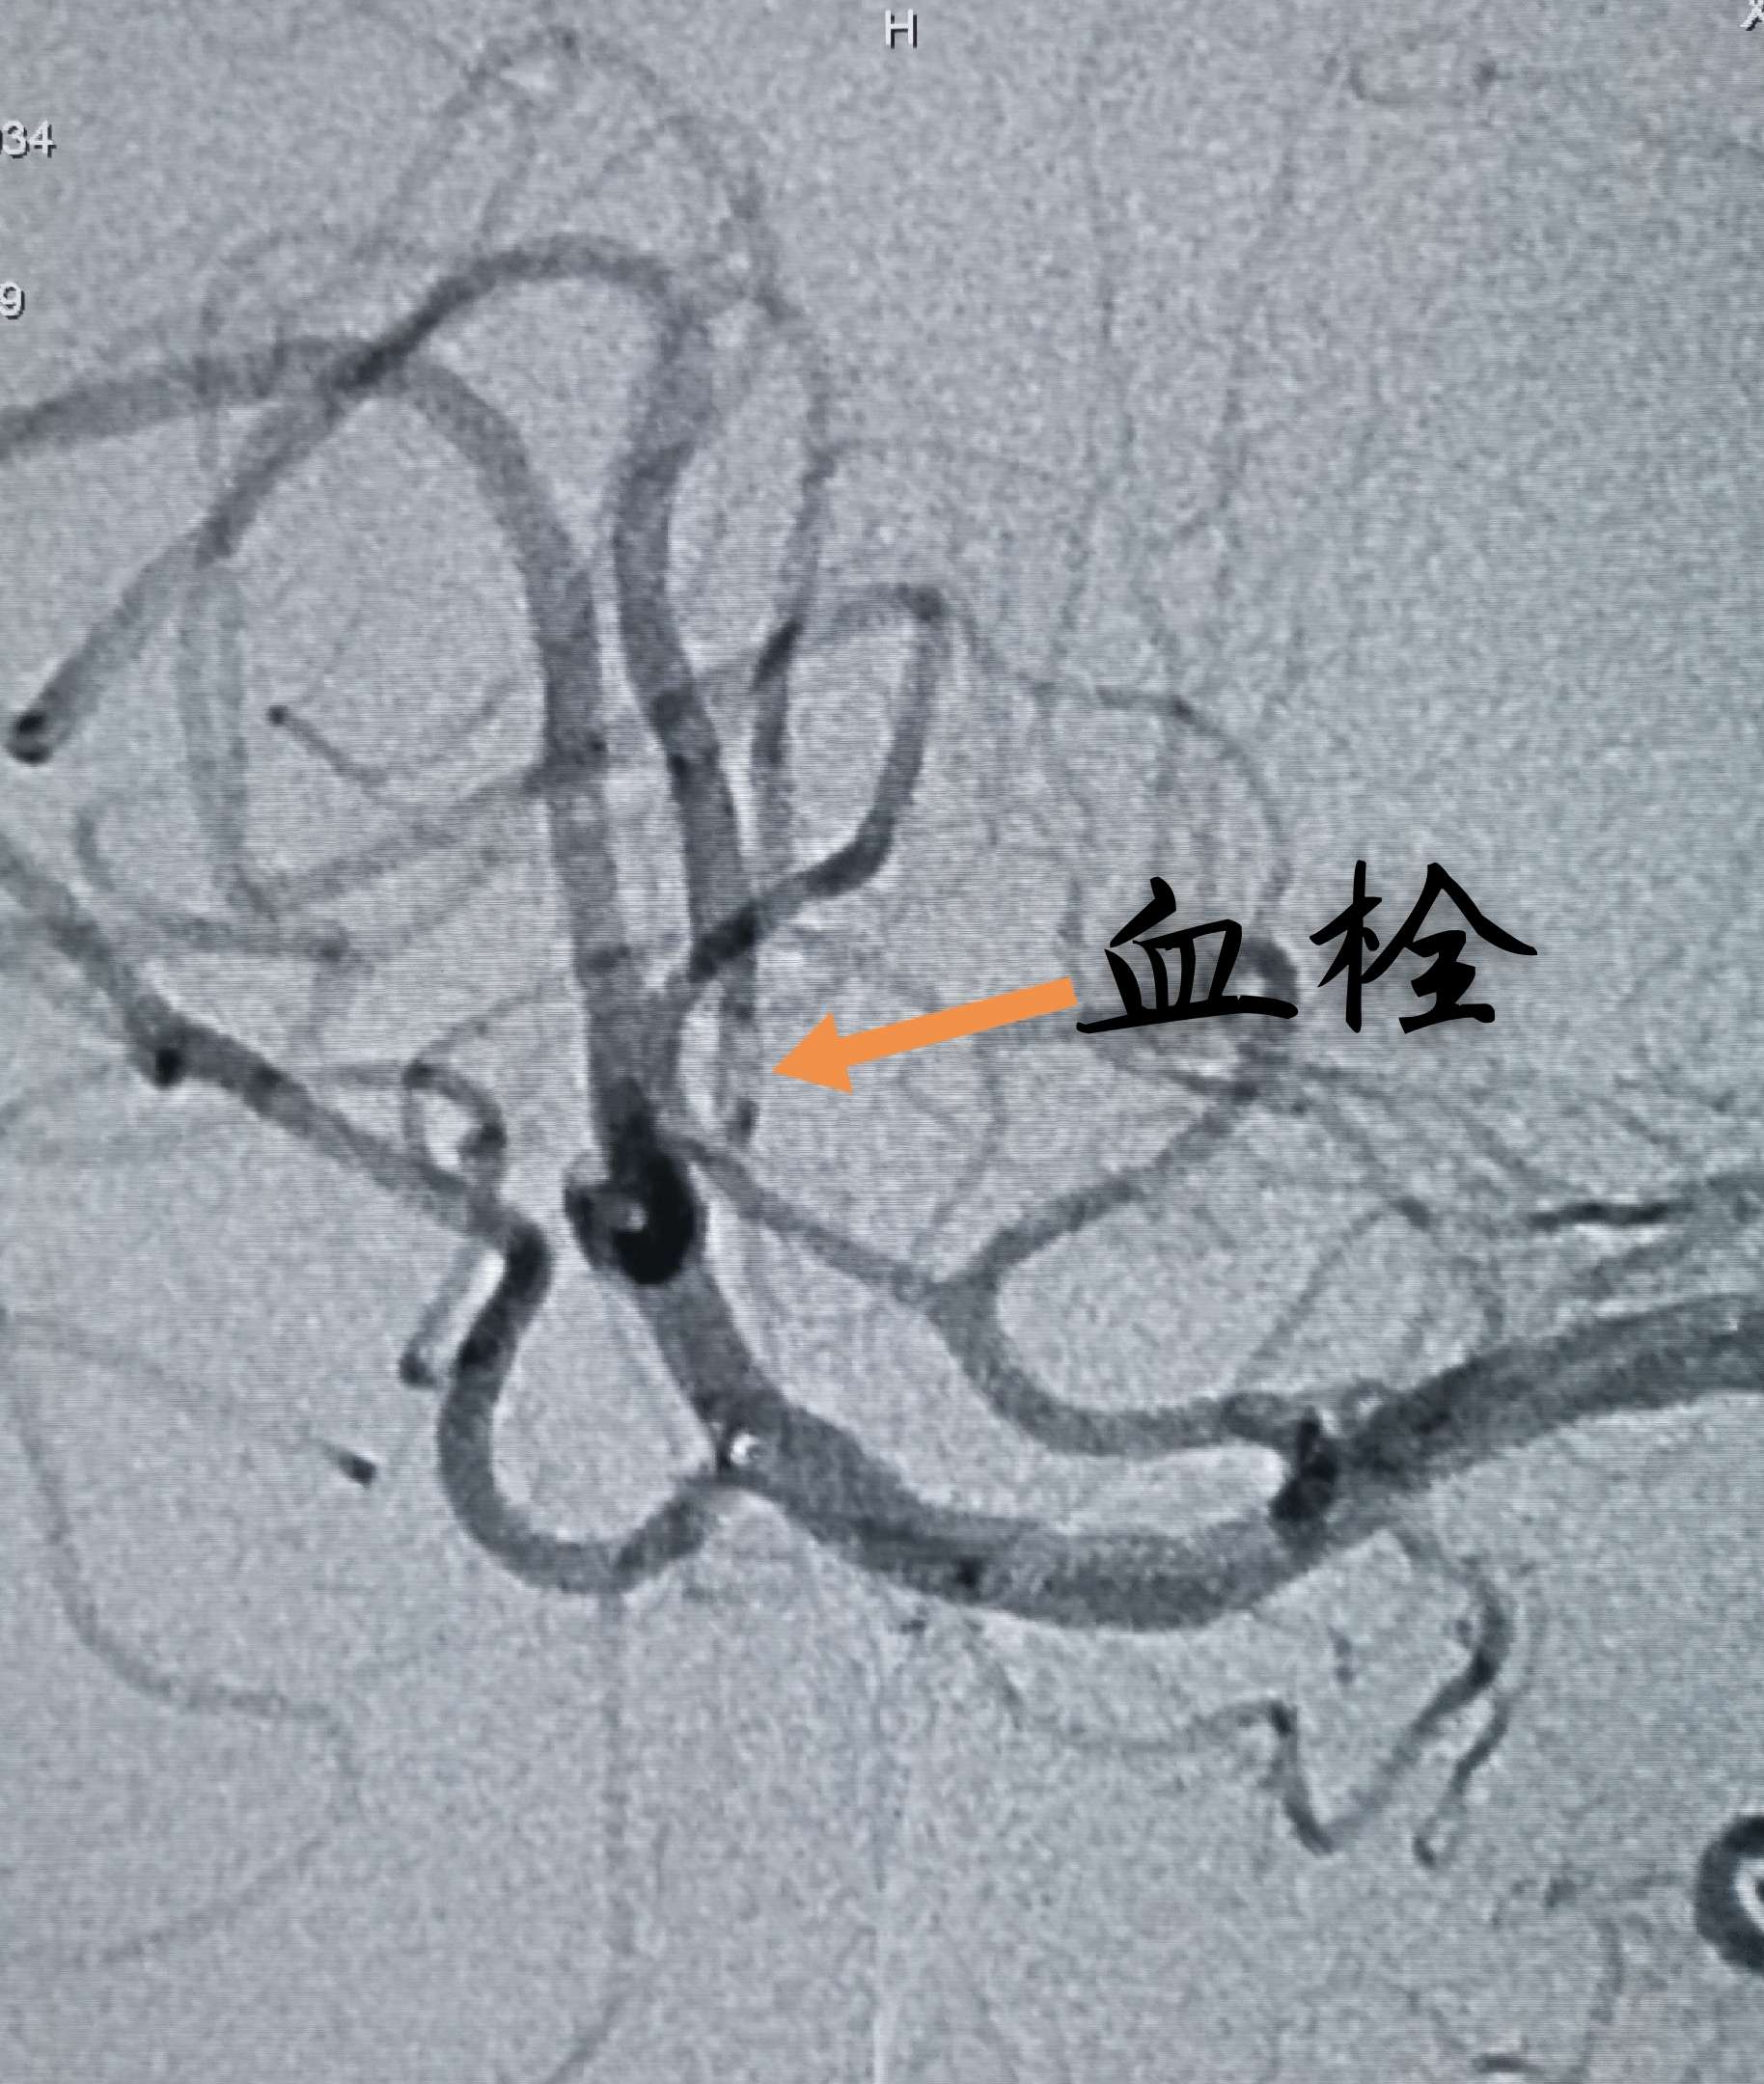

微导管造影发现血栓碎裂,并向远端逃逸

微导管内给予替罗非班0.05mg后造影,逃逸的血栓被清理

再次Guiding内造影,发现M3另一分支内仍有碎裂后逃逸的血栓

再次微导管内给予替罗非班0.05mg两次后造影,逃逸的血栓大部分被清理